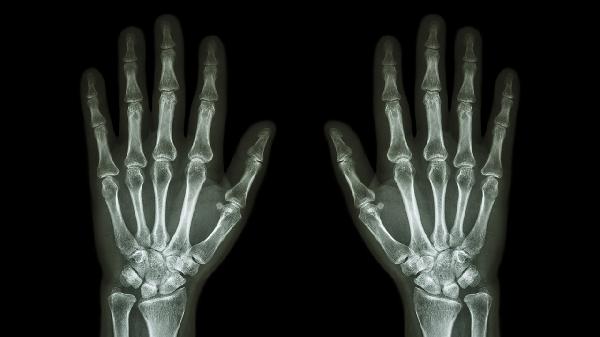

建议每日进行手指关节全范围活动训练,包括握拳、对指、分指等动作,每次10-15分钟。饮食可适当增加富含omega-3脂肪酸的深海鱼类,补充维生素D和钙质。若僵硬持续加重或伴随关节变形,应及时到骨科或风湿免疫科就诊,通过X线、磁共振或血液检查明确病因。夜间可佩戴功能性手指支具保持关节功能位,避免畸形发展。